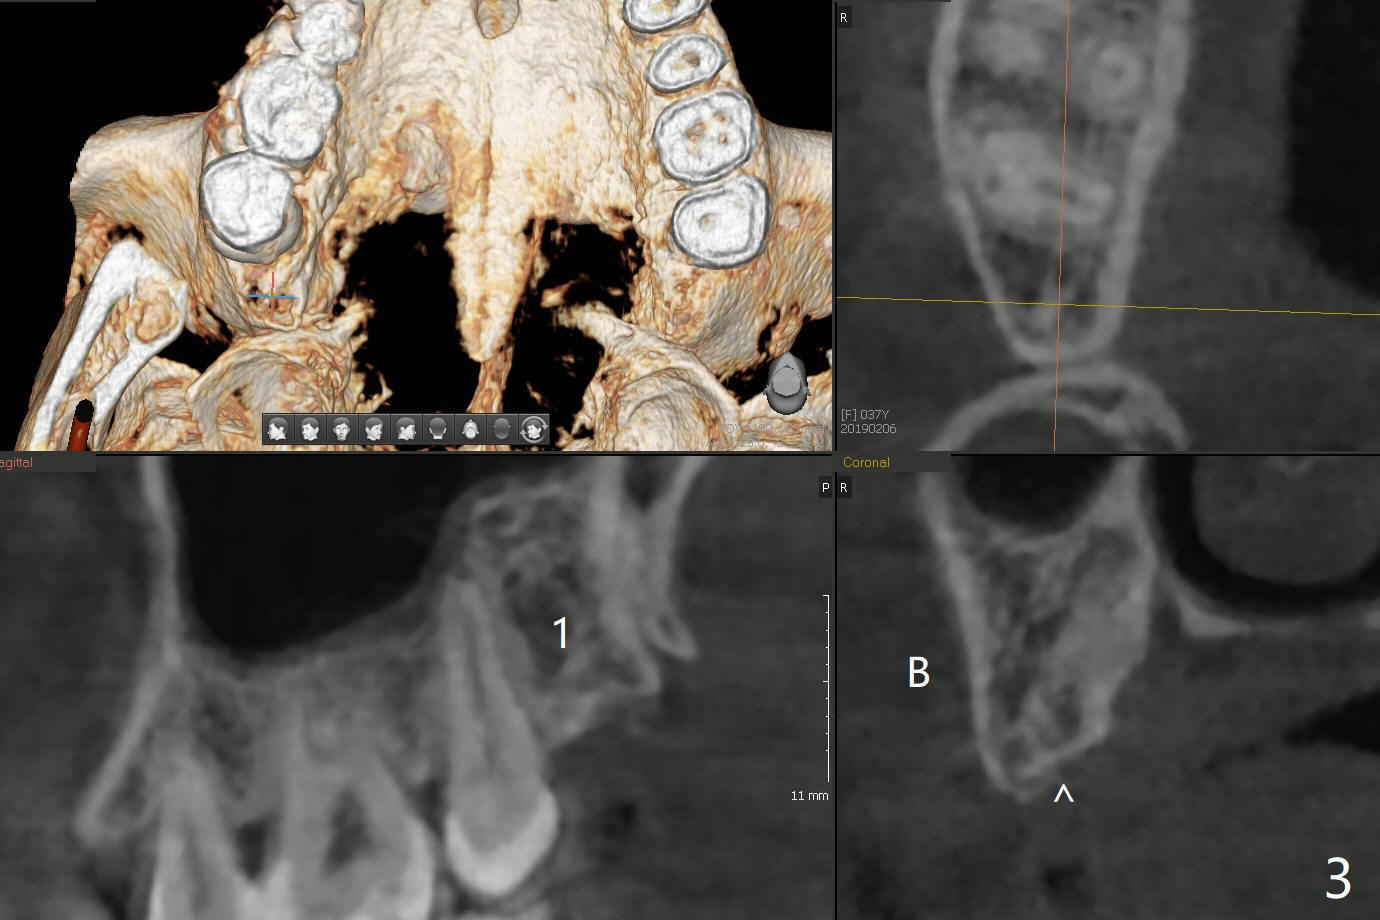

A 34-year-old lady requests extraction of #1, 16 and 32 (Fig.1). After incision for 32, surgical bur is used to create a purchase point to protect the thin bone between #31 and 32. The tooth is extracted with straight elevators and forceps. The socket is large single. Osteogen plug is placed with 4-0 plain gut suture (x4). There is cortical formation in the crest at #1, 16 and 32 three years postop (Fig.2-6 *, arrowheads). The advantage of Osteogen plug over Augma is easy placement with less risk of loss (by dissolving by saliva).